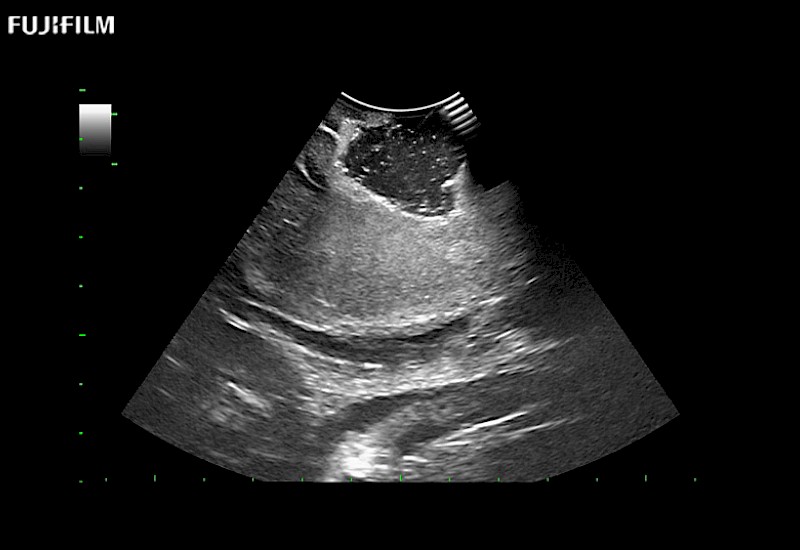

The ARIETTA 750 incorporates all of the proven technologies and functions that medical professionals have come to expect from Fujifilm Healthcare.

ARIETTA 750 is the definitive diagnostic ultrasound solution for any clinical setting - Private Office, Imaging Center, or Hospital. The ARIETTA platform provides the ultimate in clinical performance with its state-of-the-art features and large user-friendly display.

The ARIETTA 650 DI integrates the trusted technologies and features that neurosurgeons rely on from Fujifilm Healthcare.

ARIETTA 650 DI is the ideal guidance solution for the OR. The ARIETTA platform delivers exceptional clinical performance with advanced capabilities and a large, intuitive display designed for ease of use.

Guidance is the fundamental purpose for all of our surgical ultrasound technology. Fujifilm Healthcare is committed to designing tools that help neurosurgeons navigate inside the human body and provide the necessary information to immediately make critical surgical decisions.

With the ARIETTA Precision the next level of surgical ultrasound is here.